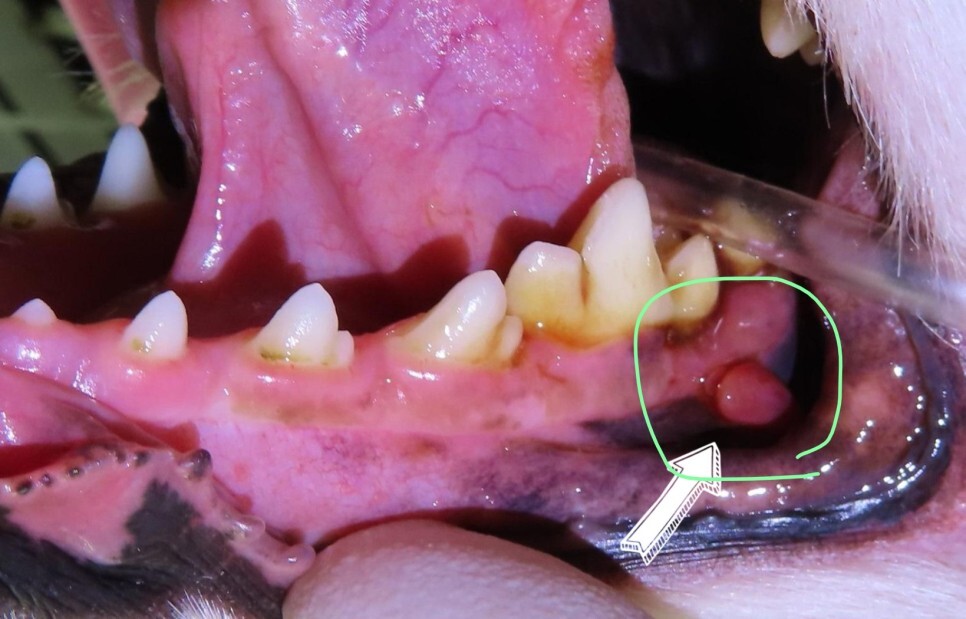

잇몸에 혹 같은 것이 난 것 같다고 하여 내원하였습니다. 종양보다는 치주염과 관련이 있을 것 같다고 설명드리고 검사를 진행하였습니다.

사진을 보면 치아 아래쪽 잇몸에 혹 비슷한 것이

관찰되고 있습니다.